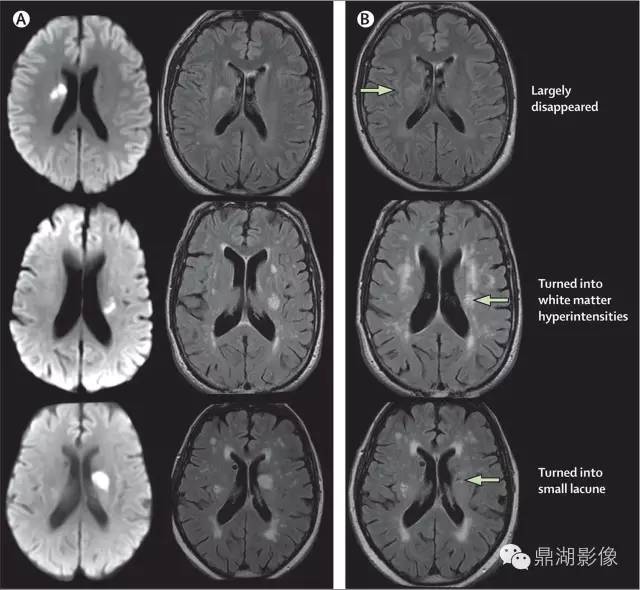

2011年,美国医学研究委员会、德国神经退行性疾病研究中心和加拿大卫生研究院共同建立了神经退行性疾病精英中心。2013年,该中心的核心专家组成员共同撰写了CSVD的共识指南,确立了代表CSVD的6种关键性损伤的神经影像学标志(图1),分别是近期皮质下小梗死、假定血管源性的腔梗灶、假定血管源性的白质高信号、PVS、脑微出血和脑萎缩。现将CSVD影像表现的相关影像技术介绍如下。

4.2.1 近期皮质下小梗死

根据2013年共识指南,近期皮质下小梗死的定义为:脑内一条穿支动脉供血区域的近期梗死,且伴有近期脑损伤一致的影像学特征或临床综合征表现。近期皮质下小梗死多发生在半卵圆中心、放射冠、基底节区、脑干等部位,MRI图像上呈T1WI低信号、T2WI高信号、FLAIR高信号、DWI高信号和GRE等信号。其轴位切面显示急性期梗死直径<20 mm,冠状位或矢状位可以>20 mm。

4.2.2 假定血管源性的腔隙灶

假定血管源性的腔梗灶定义为:圆形或卵圆形,直径为3~15 mm,分布于皮质下,充满与脑脊液相同信号,与穿支动脉供血区陈旧梗死或者出血相关。通常在FLAIR上表现为中心脑脊液样低信号,周边围绕环状高信号。但有时在FLAIR上也可表现为完全的高信号,在T1WI、T2WI上呈脑脊液样信号。

4.2.3 假定血管源性的白质高信号

假定血管源性的白质高信号定义为:脑白质异常信号,病变范围大小不等,在T2WI或FLAIR上表现为高信号,无腔隙,T1WI上呈等信号或低信号(不及脑脊液)。除非特别说明,皮质下灰质病变及脑干病变不属于白质高信号。假定血管源性的白质高信号的提出,排除了由其他非血管源性疾病所致的白质病变,如多发性硬化、白质营养不良等。

目前对脑白质高信号的影像学评价方法很多,主要有半定量和定量评估。半定量方法主要有Fazekas直观评分量表(图2)、年龄相关脑白质改变(ARWMC)量表、Scheltens量表。其中,Fazekas直观评分量表临床最常用,ARWMC量表可结合病变部位进行分析,能提供更多有效信息。定量方法包括Kropper法和FreeSurfer法,主要利用全自动定量分析软件对扫描后的头颅MRI图像进行分析,通过识别病变区异常信号、勾选病变区、计算病变体积来进行定量分级,从而定量评估白质病变的严重程度。

4.2.4 PVS

指南对PVS的定义为:穿过灰质或白质,与常见血管走行一致的充满液体的间隙。PVS扩张在MRI上主要表现为直径<3 mm的圆形、卵圆形或线形的,T1WI上低信号、T2WI上高信号(与脑脊液信号强度一致)、FLAIR上低信号、DWI上无弥散受限的病灶,通常边界清晰、无对比剂增强效应和占位效应。病灶形状取决于成像平面,成像平面与血管走行平行时呈线性,与血管走行垂直时呈圆形或卵圆形。该征象多见于基底节区靠近前联合附近、脑凸面皮层下、半卵圆中心、脑干及外囊,很少出现在小脑,常与假定血管源性的腔隙灶同时出现,需加以鉴别。普遍接受的用来区分两者的特点是PVS直径一般不超过3 mm,且在T2WI和FLAIR上不表现为围绕脑脊液样信号的环状高信号,除非间隙跨越白质高信号区。

4.2.5 脑微出血

脑微出血定义为在顺磁敏感的序列如T2加权梯度回波序列或SWI上表现为小的(通常直径为2~5 mm,有时达10 mm)散在低信号,对磁化效应敏感。病灶通常边界清楚、均质,在T2加权梯度回波序列上有高光溢出效应(指影像学上显示的微出血面积比实际含铁血红素沉积面积大)。需要鉴别的可能出现类似病灶的情况有铁和钙沉积、骨、正常血管断面的流空效应、弥漫性轴索损伤等。此外,还要区分小的陈旧性的深部自发性脑出血,其范围相比脑微出血更大,有不规则囊腔,且在T1WI上可见。常用的直观定量脑微出血的方法包括微出血解剖评分量表和观察者脑微出血评分量表。计算机自动分析是近年研究热点,它可以缩短评估时间,减少个体间评估差异。

4.2.6 脑萎缩

2013年的共识指南将脑萎缩定义为与特定的局灶性损伤,如脑外伤或脑梗死无关的脑容积减少。脑萎缩可以是广泛的或局部的(如特定的脑叶或海马等特定区域),可以是对称或不对称的,亦可以是组织选择性的(如发生在白质等某一特定组织层)。目前不同部位的脑萎缩有相应的诊断标准,全脑皮层萎缩分级用于评价全脑(图3);内侧颞叶萎缩分级主要评价颞叶内侧,重点是海马(图4);Koedam分级主要评价顶叶,尤其是扣带回和楔前叶(图5);Kipps/Davies分级主要评价额颞叶(图6)。推测脑组织减少是由脑沟(周围)和脑室(中心)的脑脊液空间相对于颅内容积扩大所引起的。